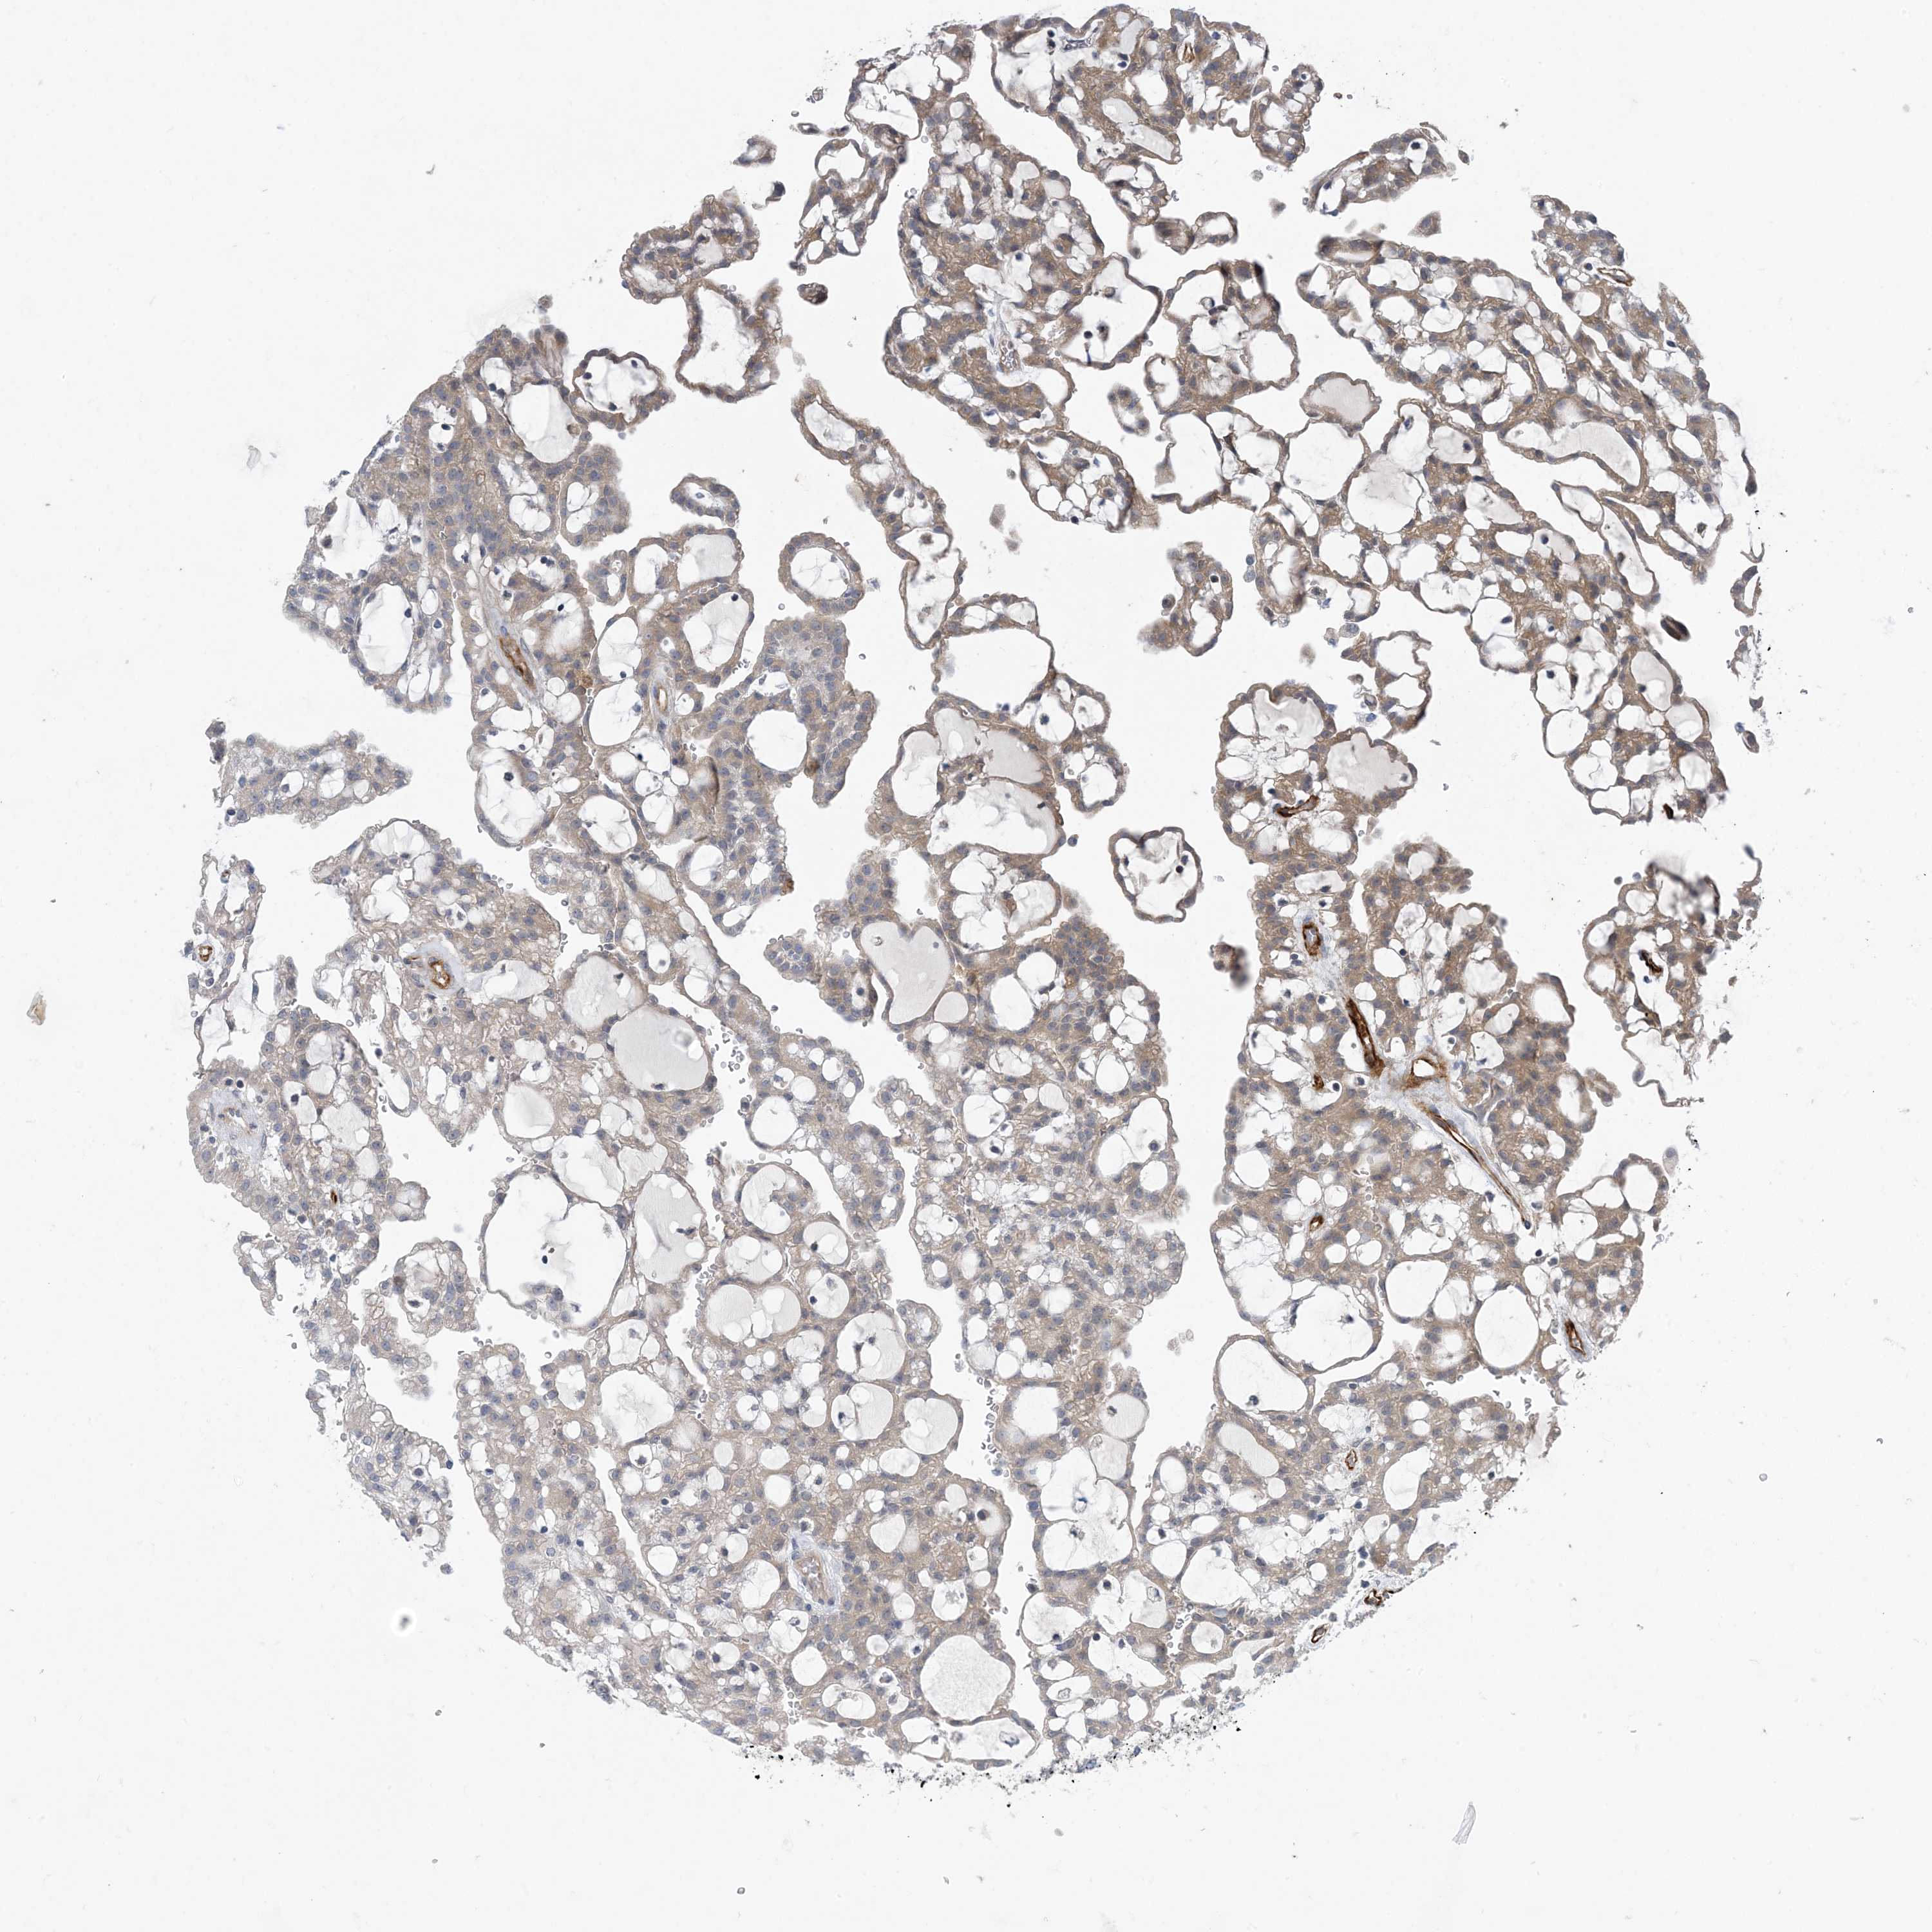

KIDNEY RENAL CLEAR CELL CARCINOMA (TCGA) - Interactive survival scatter ploti

The Survival Scatter plot shows the clinical status (i.e. dead or alive) for all individuals in the patient cohort, based on the same data that underlies the corresponding Kaplan-Meier plots. Patients that are alive at last time for follow-up are shown in blue and patients who have died during the study are shown in red.

The x-axis shows the expression levels (FPKM) of the investigated gene in the tumor tissue at the time of diagnosis. The y-axis shows the follow-up time after diagnosis (years). Both axes are complimented with kernel density curves demonstrating the data density over the axes. The top density plot shows the expression levels (FPKM) distribution among dead (red) and alive patients (blue). The right density plot shows the data density of the survived years of dead patients with high and low expression levels respectively, stratified using the cutoff indicated by the vertical dashed line through the Survival Scatter plot. This cutoff is automatically defined based on the FPKM cutoff that minimizes the p-score. The cutoff can be changed by dragging the vertical line or by entering a cutoff value in the square labeled "Current cut-off".

Under the Survival Scatter plot the p-score landscape (black curve; left axis) is shown together with dead median separation (red curve; right axis). Dead median separation is the difference in median mRNA expression between patients who have died with high and low expression, respectively. It is calculated as follows: median FPKM expression of dead patients with high expression - median FPKM expression of dead patients with low expression. This is intended to aid the user in visually exploring custom cutoffs and the associated p-scores and dead median separation.

Individual patient data is displayed and can be filtered by clicking on one or more of the category buttons on the top of the page. Categories describing expression level and patient information include: high, low, alive, dead, female, male and tumor stages. The scale of the x-axis can be toggled between linear and log-scale by clicking on the "x log" button. Mouse-over function shows TCGA ID, patient information and mRNA expression (FPKM) for each patient.

& Survival analysisi

Kaplan-Meier plots summarize results from analysis of correlation between mRNA expression level and patient survival. Patients were divided based on level of expression into one of the two groups "low" (under cut off) or "high" (over cut off). X-axis shows time for survival (years) and y-axis shows the probability of survival, where 1.0 corresponds to 100 percent.

HIKESHI is not prognostic in Kidney Renal Clear Cell Carcinoma (TCGA)

Best expression cut offi

Based on the FPKM value of each gene, patients were classified into two groups and association between prognosis (survival) and gene expression (FPKM) was examined. The best expression cut-off refers the FPKM value that yields maximal difference with regard to survival between the two groups at the lowest log-rank P-value. Best expression cut-off was selected based on survival analysis .

When clicking on this number, the vertical dashed line indicating cut-off, the interactive survival plot, and the Kaplan-Meier curve will be adjusted to show results based on the best expression cut-off.

: 26.49

Average pTPM 26.5

Number of samples 521